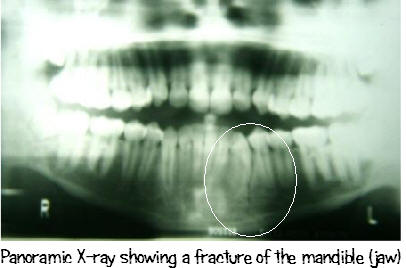

The panoramic x-ray has many other applications such as revealing past or present TMJ (jaw joint) disorders, those who require full or partial removable dentures, dental implants, or braces. This type of x-ray is also helpful for patients who are at risk or suspected of having oral cancer or other tumors of the jaw, have impacted teeth (especially wisdom teeth), have had any recent trauma to the face or teeth (i.e. can help identify a fractured jaw), and for those who can not tolerate other types of films (severe gaggers).

A Panoramic x-ray gives you a big picture view

of the entire mouth!